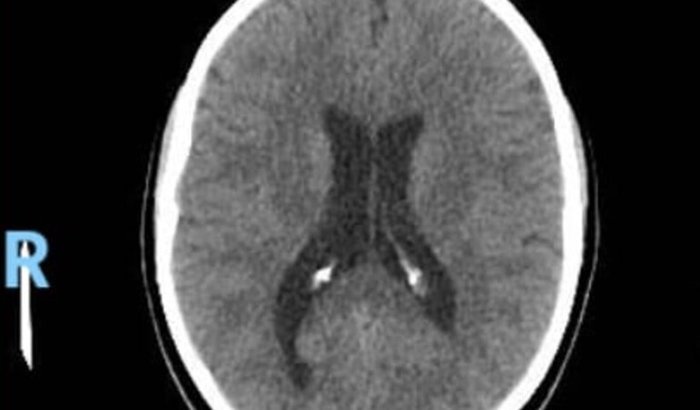

Descrição:Minha irmã Thamires tem sofrido com fortes dores de cabeça devido a uma má-formação no ventrículo cerebral. Desde pequena ela convive com essa condição sem saber, mas agora, com o corpo mais maduro, os sintomas se tornaram intensos.Cada esforço físico, cada momento em que o corpo precisa de mais oxigênio, gera dores intensas e desconforto, pois o ventrículo aumentado pressiona áreas do cérebro e atrapalha as funções normais.